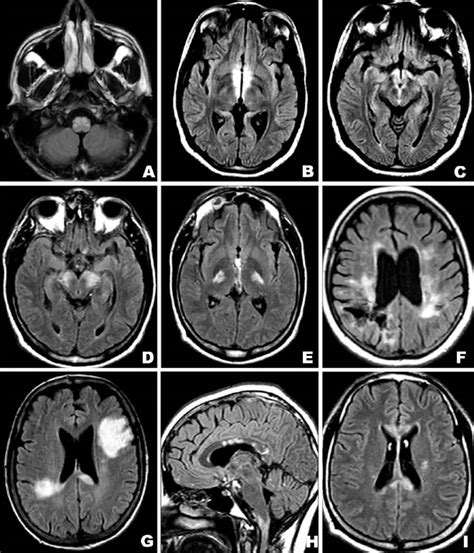

• Brain Lesions: These are abnormalities in the brain tissue and can be caused by tumors, infections, or trauma. Brain lesions can affect cognitive function, motor skills, and sensory perception.

• Imaging Techniques: Imaging tests such as X-rays, CT scans, MRIs, and ultrasounds can provide detailed images of internal lesions. These tests are particularly useful for detecting lesions in organs and the brain.